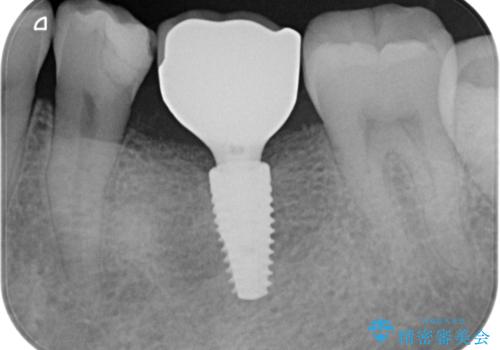

[乳歯の晩期残存] 歯周組織再生療法を併用したインプラント治療

- 右下に残っている乳歯がぐらつくことの治療を希望され来院されました。

乳歯は残すことが難しい状態なので抜歯を選択、抜歯後の治療法としてブリッジではなくインプラント治療を希望されたのでインプラントを用いたかみ合わせの回復を計画します。

後に生えてくる永久歯がもともとない等の理由で乳歯が大人になっても残ってしまうことがあります。(乳歯晩期残存)

問題なく噛むことができればよいですが、揺れてきたり痛みを感じるような場合は抜歯が必要であることが多いです。

今回の症例では乳歯の後ろの根が大臼歯近くの骨を溶かしてしまっている状況だったので、かみ合わせの回復を目的としてインプラントを埋入する際に同時に骨の吸収している部分にエムドゲイン塗布と他家骨填入を行い再生治療を同時に行いました。